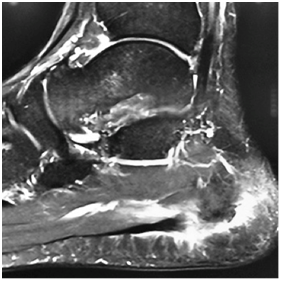

After the 5th week of rehabilitation without jumping restrictions, magnetic resonance (MR) control was requested, showing a thickening of the plantar fascia next to its calcaneal insertion with a maximum thickness of 9 mm showing increased signal intensity with healing of its fibers in its portion More medial (Figure 4) (Figure 5). There is evidence of plantar fascia thickening next to its calcaneal insertion with 9 mm of thickness. After confirming the healing process, the athlete was available to the technical committee for training and games at the end of the 5th rehabilitation week.

Figure 4, 5 Magnetic resonance control with T2-weighted multiplanar FAT SAT sequences.